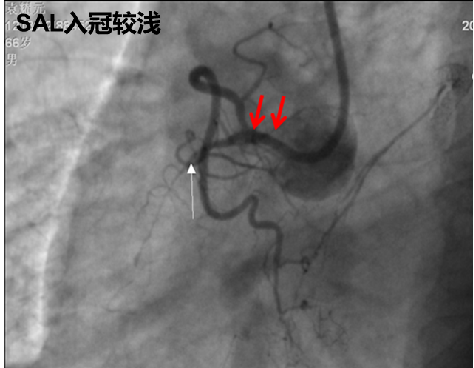

SAL头端入冠不深,几乎没有嵌顿现象,可避免刮伤主动脉窦,避免损伤靶血管和主动脉壁。

灵活操作

SAL指引导管在主动脉窦里可自如转动,入冠和撤出操作较简单,术者可灵活调整以适应不同右冠解剖形态及头臂干异常。

SAL0.75指引导管到位:坐到右窦底边顺时针旋转边上提。